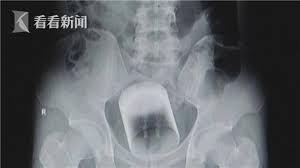

O echipă de medici din China a declarat ulterior că bărbatul a reclamat o constipaţie dureroasă abia după două zile de la întâmplare, dar chiar şi atunci, nu a mărturisit cum s-a putut întâmpla un astfel de incident. În cele din urmă, medicii din Shanghai au reuşit să extragă cana fără să o spargă. Bărbatul din Guangzhou s-a prezentat la spital reclamând nişte dureri insuportabile, informează Rador.

Medicii se temeau că obiectul s-ar putea sparge în rectul pacientului, însă operaţia a evoluat fără alte incidente.